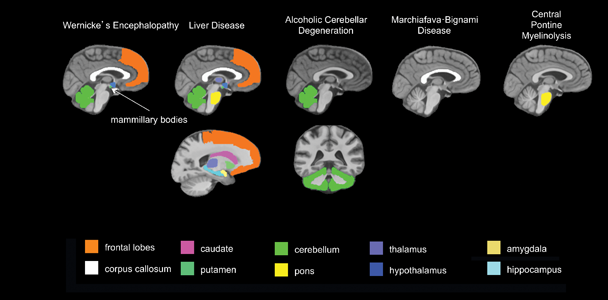

To evaluate alcohol’s central nervous system effects, researchers distinguish “uncomplicated alcoholism” (i.e., alcohol use disorder [AUD]) from the various clinically diagnosable consequences of chronic alcohol consumption, including Wernicke’s encephalopathy (WE), Korsakoff’s syndrome (KS), hepatic encephalopathy (HE), central pontine myelinolysis (CPM), alcoholic cerebellar degeneration (ACD), alcohol-related dementia (ARD), and Marchiafava-Bignami disease (MBD).1 The use of brain-imaging technology to evaluate clinically defined syndromes associated with chronic alcoholism, each with relatively unique radiological signatures (see table 1 and figure 1), provides guideposts for studying brain alterations associated with uncomplicated alcoholism.

1 WE and KS are neurological disorders caused by thiamine deficiency. HE is a decline in brain function as a result of severe liver disease. CPM is a neurological disorder resulting from the destruction of the myelin layer that covers nerve cells in the pons. ACD occurs when neurons in the cerebellum are damaged due to alcohol use. MBD is a neurological disease associated with alcoholism, caused by damage to the corpus callosum.

Table 1 Radiological Signatures in Brain Imaging of Patients with Alcoholism-Related Syndromes

|

Alcoholism-Related Syndrome |

Abbreviation |

Primary Targeted Region(s) |

Secondary Targeted Regions |

Prevalence in Alcoholics (Percentage) |

|---|---|---|---|---|

|

Wernicke’s Encephalopathy |

WE |

Mammillary bodies, periaqueductal gray matter, dorsal medulla, tectal plates, olivary bodies, pons, tissue surrounding 3rd ventricle |

|

12–18 |

|

Korsakoff’s Syndrome |

KS |

Mammillary bodies, hippocampus, thalamus, orbitofrontal cortices |

Cerebellum, pons |

10–15 |

|

Hepatic Encephalopathy |

HE |

Globus pallidus, substantia nigra |

Corticospinal tract, cortex |

3–16 |

|

Central Pontine Myelinolysis |

CPM |

Pons |

Basal ganglia, thalamus, cerebral gray–white matter junctions |

< 0.5 |

|

Alcoholic Cerebellar Degeneration |

ACD |

Cerebellum |

|

0.4–42 |

|

Alcohol-Related Dementia |

ARD |

Frontal cortex |

|

3–24 |

|

Marchiafava-Bignami Disease |

MBD |

Corpus callosum |

Cortex |

< 0.002 |